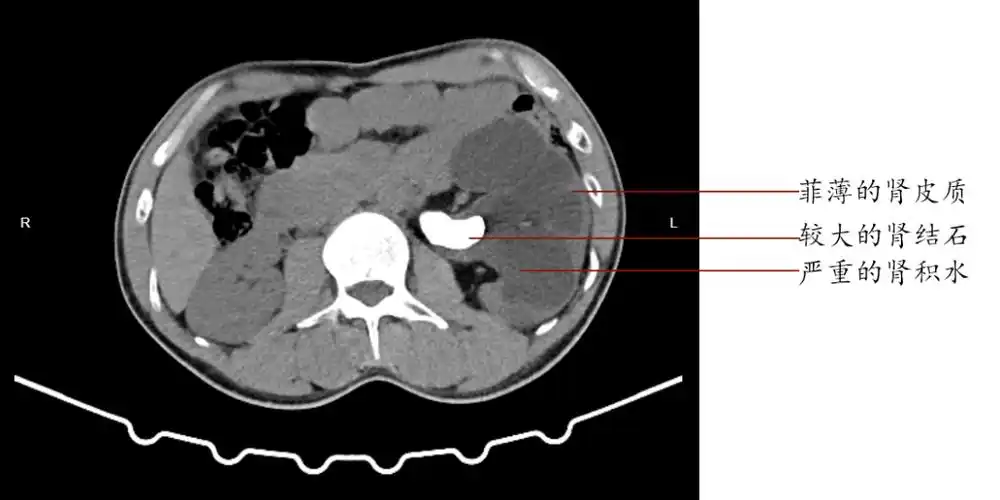

被冷处理的沉默结石竟令男子左肾几乎报废

肾结石的硬度已经颠覆了医生的认知,肾结石的ct值了解一下

肾结石输尿管结石的ct及kub阅片

最新进展 > 正文 后进行ct平扫时,除了发现左侧肾盂结石以外,细心的